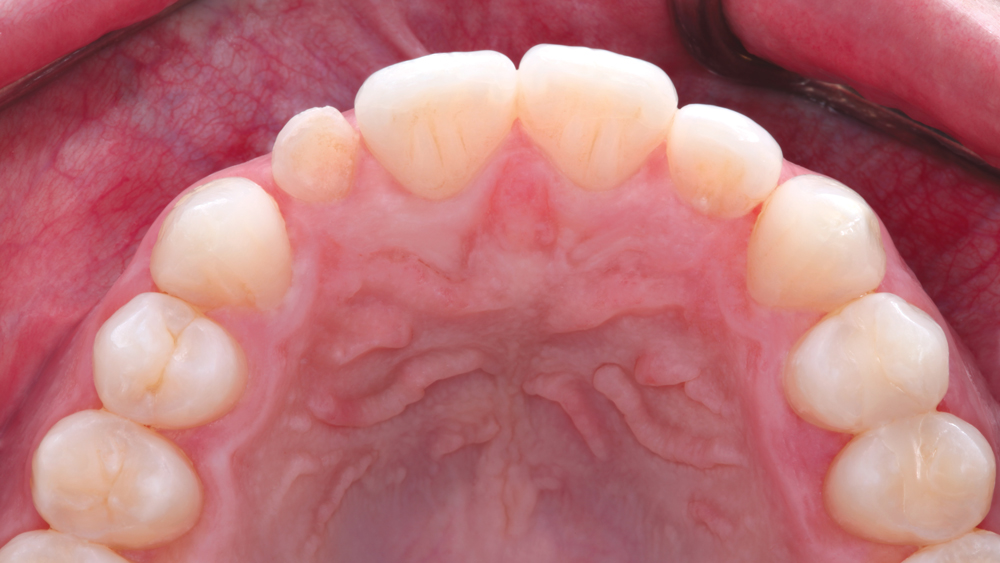

The following case illustrates the efficient, straightforward clinical workflow for placing Hahn Tapered Implants via guided surgery. A digital treatment plan is developed in which a 3.5 mm implant is positioned to support the ideal prosthetic outcome. An immediate provisional crown is designed in concert with the surgical guide and delivered at the time of surgery, helping to produce a predictable, highly esthetic restoration for a demanding case in the smile zone.